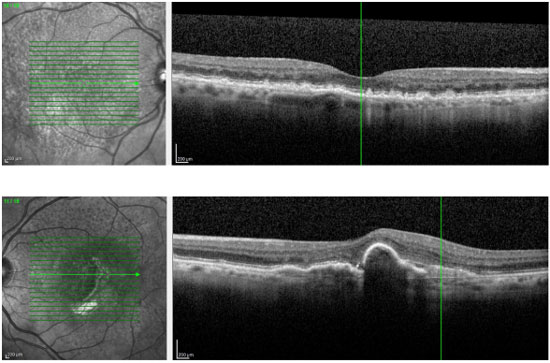

2) Descolamento do Epitélio Pigmentado (DEP) enrugado tem melhor prognóstico do que DEP alto e liso quando tratado com anti-VEGF

Mimoun e cols. da Universidade de Paris-Est, avaliaram 29 olhos com DEP enrugado e 23 olhos com DEP liso, tratados com anti-VEGF por 4 anos. A visão ao final do seguimento foi estatisticamente melhor no grupo com DEP enrugado (log MAR 0.36) quando comparado com DEP liso (log MAR 0.62) – p=0.01